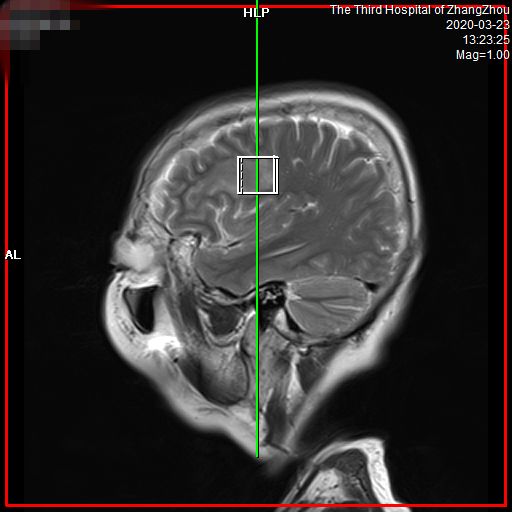

介绍之前,先抛一张我的“帅气照”。

德国西门子3.0T磁共振

我是新一代的聚能光谱磁共振

MAGNETOM Spectra 3.0T

图像更清晰、诊断更精准

• 图像更清晰,病变细节显而易见。对中枢神经系统如头、颈部疾病,以及腹盆部、骨肌系统、乳腺等区域病变检出更敏感,可早发现、早诊断和早治疗。

• 信噪比高,能更早发现小病灶。有关数据显示,对于各类疾病,特别是神经系统和体部系统疾病,可以提前发现病灶,给患者治疗带来了充分的时间,大大提高了病变的诊断水平,让疾病无处可逃,为广大患者带来福音。